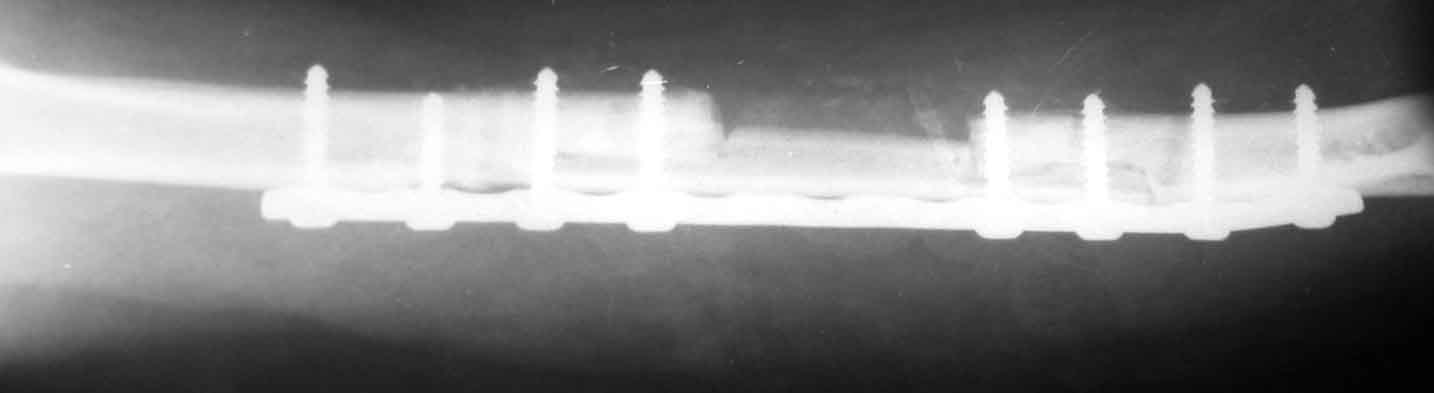

Уважаемый Александр.Несколько поздно решил написать.При дефектах после любых повреждений мы предпочитаем аутопластику из малоберцовой кости по типу русского замка.Предплечье не нашел на рентгене,но зато нашел плечо.Я думаю Вы все поймете.С уважением .

Кликните для загрузки файла Рисунок2.jpg